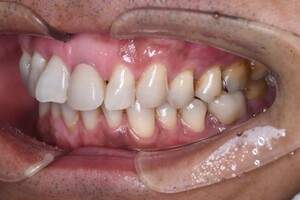

症例2

治療前

治療後

治療内容

奥歯はアマルガムという発ガン性があると言われている銀の素材を金銀シルバーインレーに変えました。前歯は金属を使用した歯でややまわりのご自身の歯より色がういていたので、周りの歯にあわせて透明感のある仕上がりのある材料にてやり変えました。

治療期間 1ヶ月

治療費 合計:990,000円 (内訳)

ジルコニアボンド:165,000円×6本

治療のリスク・副作用 被せ物を外すと、ご自身の歯が少ない場合は別途はを残すための処置が必要になることがあります。